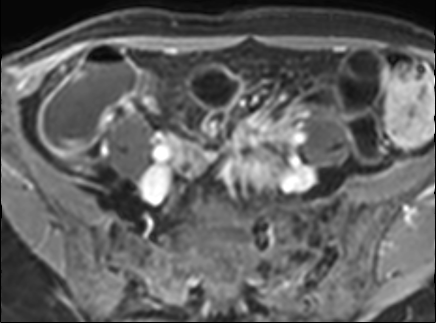

Kiểu ngấm thuốc phân lớp tại trực tràng kèm một ít mờ mỡ xung quanh trên hình ảnh T1 axial sau tiêm thuốc tương phản từ (mũi tên). Tình trạng viêm liên tục với kiểu ngấm thuốc đồng nhất có thể thấy tại đại tràng sigma (mũi tên xanh lá). Ngoài ra, có một nang phần phụ bên phải với viền ngấm thuốc (đầu mũi tên).

Kiểu ngấm thuốc

phân lớp

Kiểu này gợi ý hoạt động bệnh nặng hoặc bệnh mạn tính kéo dài (4,5).

Hình ảnh ba lớp được tạo ra do niêm mạc và thanh mạc ngấm thuốc mạnh trong khi lớp giữa không ngấm thuốc, bao gồm lớp dưới niêm mạc và lớp cơ.

Lớp giữa này có thể chứa mỡ, phù nề hoặc mô xơ.

Có thể phân biệt các thành phần này bằng chuỗi xung T2 có fat-sat.